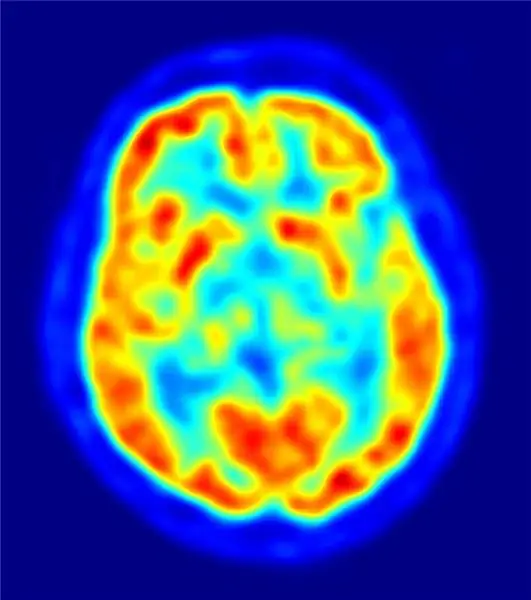

Что действительно интересно в этом опыте, так это увидеть, как все восприятие мира меняется в зависимости от того, что происходит в мозгу. И те вещи, которые происходят в мозгу, могут не иметь реальной причины.

Йенс Маус (https://jens-maus.de/) - собственная работа, общественное достояние, ссылка

В некотором смысле наше восприятие никогда не бывает точным. В каком-то смысле объективной реальности не существует. Все, что мы видим и чувствуем, фильтруется через множество вещей в нашем мозгу. Любая вещь, отличающаяся от нашего нормального темперамента, может иметь глубокие изменения в том, как мы воспринимаем то, что происходит с нами в жизни. Подруга недавно рассказала мне о своей матери, у которой случился инсульт. Это изменило ее личность. Она превратилась из любящей, доброй и понимающей в критичную, злую и резкую.

Страшно осознавать, как мало мы на самом деле контролируем свой мозг. Часть цели в индуизме состоит в том, чтобы контролировать свой разум, не подчиняться этим колебаниям в химии мозга. Я думаю, это самое сложное, чего требует от нас индуизм.

Как мы можем сделать этот шаг назад и вспомнить, что то, что наш мозг считает реальностью, может быть неточным, и что через час этот мозг может говорить нам совсем другое? И если мы не можем доверять собственному восприятию, то чему мы можем доверять?